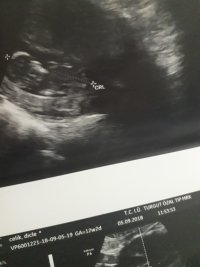

Nub teorisiyle cinsiyet tahmini bebeğim erkek mi kız mı ?

Banada yorum.yapin lutfen 12 haftaligiz

Nub teorsisi için cinsiyet tahmininde yorum isteyen arkadaşlar lütfen uyarımızı dikkate alın. Ultrason görüntüleri elinize ilk verildiği gibi net olmaz. Sık sık ışığa maruz kaldığı için görüntü kalitesi bozuluyor dolaysıyla bizlerde değerlendirme yapamıyoruz. Sizlere yorum yapabilmemiz için görüntü kalitesi aşağıdaki linkte yer alan görseller gibi olmalıdır. Ayrıca Bebeğin cinsiyeti net olarak 18-19-20. haftalarda belli olur..

Merhaba, yüklediğiniz görsellerde nub çıkıntısı anlaşılmıyor , dolaysıyla değerlendirme yapamıyoruz.. Görselin kalitesi aşağıdaki gibi olmaldır.. Sağlıklı gebelik süreci diliyorum.